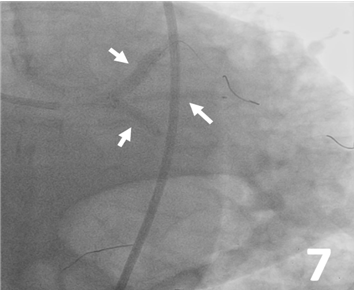

Predilatation was made from the LAD, ramus, and LCx to the left main artery with 3 Ryurei balloons (Terumo) at 8 atm (3.5 x 20 mm, 2.5 x 20 mm, and 2.5 x 15 mm, respectively) (Figure 5). A 3.0 x 32-mm synergy stent was deployed from the middle to the proximal segment of the LAD (Figure 6). Then, 3 stents were advanced and deployed simultaneously from the LAD, ramus, and LCx (Synergy 5.0 x 24 mm [Boston Scientific], Xience Sierra 3.0 x 33 mm [Abbott], and Synergy 3.5 x 16 mm, respectively) (Figure 7). Simultaneous triple-balloon (kissing) inflation at 12 atm was performed with three 2.0 x 15-mm Ryurei balloons (Figure 8); the 3 balloons were simultaneously inflated 3 times.